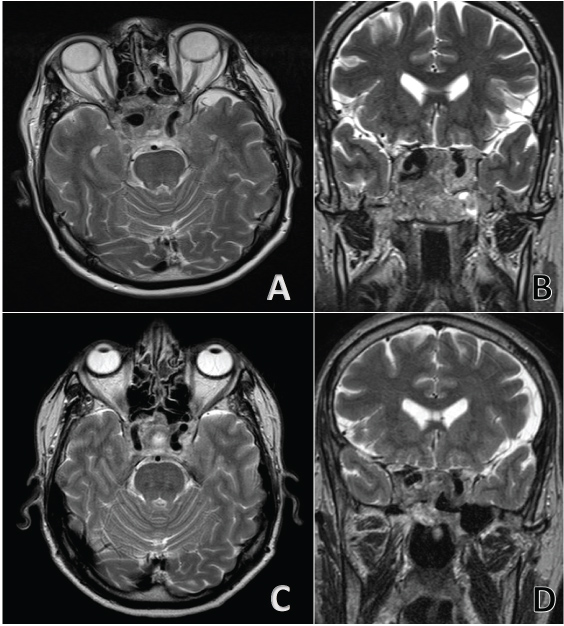

Non-contrast head CT revealed a large destructive central skull base mass with hyperdensity in his context. A further examination with pre-and post-gadolinium brain MRI, underlined the limits of the skull base mass centred in cellar region with erosion of sphenoid sinus and clivus. It was extended inferiorly to the magnum foramen and occipital condyles, laterally to the petrous apices, sigmoid sinus and jugular bulbs; superiorly occupying the chiasmatic cistern, encasing optic nerves and both internal carotid arteries (Figure 1). A large flow void, within the region of the right carotid siphon has been shown (Figure 2). Digital subtraction angiography (DSA) was performed that confirmed a pseudo-aneurysm of cavernous segment of right ICA with a bleb on the anterior side (Figure 1).

Figure 2: Non-Contrast T2-weighted MRI comparates pre-treatment (A,B) and post-treatment (C,D). View Figure 2